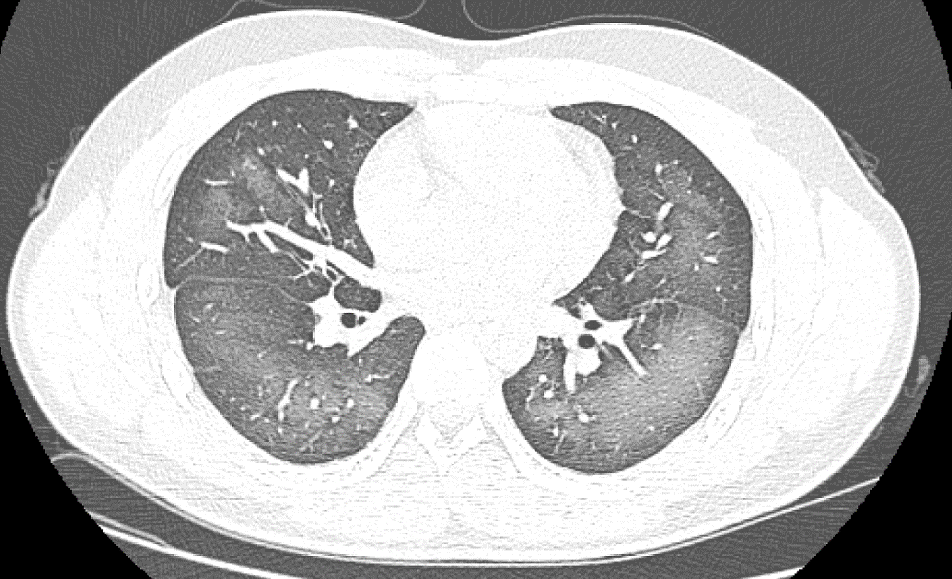

经检查,肺部CT片显示,李林双肺赫然呈现大范围白色样病变,报告提示“白肺”。

“白肺”一般是指重症肺炎在X线或CT检查下的表现,患者肺部呈现一大片的白色状态,往往会出现呼吸困难、呼吸衰竭,严重者还会出现其他脏器功能障碍。

长沙市第三医院放射影像科的接诊医师表示,除了感染、弥漫性肺泡出血综合征等“白肺”最常见的病因外,吸入有害物质如粉尘、喷雾等,也可导致肺部出现大范围白色样病变。这位年轻的患者就是因为使用不当,吸入了一部分防晒产品进入肺部,导致“白肺”的发生。